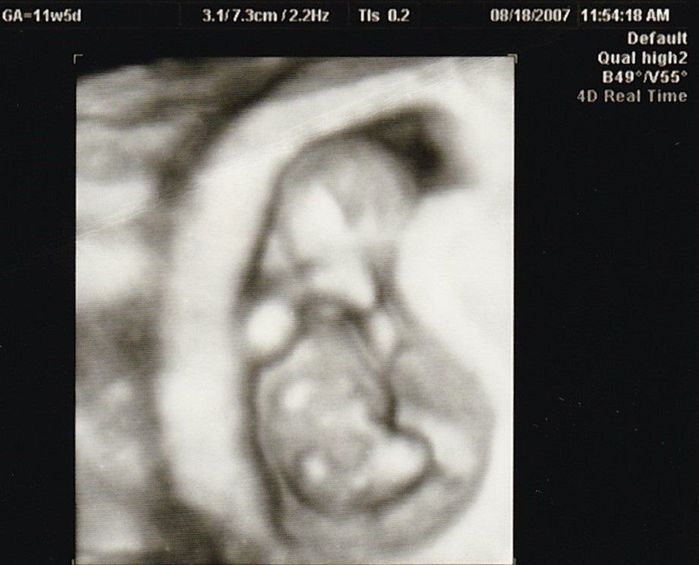

妊娠11週目のエコー写真

産院では、動画で赤ちゃんが動く映像を見せてくれて、検診に行くのが楽しみでした。

この頃、胎児染色体検査(ダウン症かどうかの検査)をするかを決めたり、“ソフロロジー法”の資料を読んだりすることで、私はどういう出産をしたいかを考えるようになりました。(胎児染色体検査はその結果によって産むか産まないかを考えることをしたくなかったので、受けるのをやめました。)